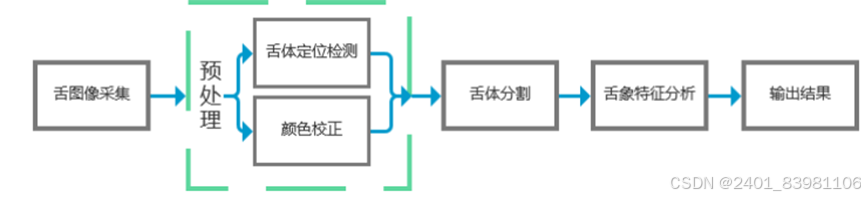

### 舌象采集:

### 舌象分割:

图像分割:基于深度学习的舌头图像分割模型主要分为两类, 82 一个是U-Net83,84和 Seg-Net85,86从全卷积网络(FCN)演化而来,另一个是从CNN改进而来的Mask R-CNN, 87 广泛应用于各种类型的医学图像分割

进行光补偿、色彩校正、 几何变换等光补偿在图像处理中应用广泛,常见的光补偿方法有Gray World色彩均衡算法和基于白色参考图像的算法:Yu et al. 47 提出了一种在没有白色参考图像的情况下消除光不平衡的方法,即通过分割图像,估计不同背景图像的光差,然后进行光补偿来获得背景。该方法可用于分割显微医学图像以及其他医学图像。相机采集的舌头图像由于照明不均匀而产生噪点,严重影响图像质量。 48 这可以通过阈值化、扩大对比度、降低灰度值和滤除噪声等方式在低级图像处理、图像的点处理、图像的中值滤波等方面来完成。该方法可以减少预处理过程中产生的偏差,同时提高图像处理速度色彩校正主要包括环境光照条件校正、色彩空间校正、色卡色彩校正和算法校正

2. **分割技术**: